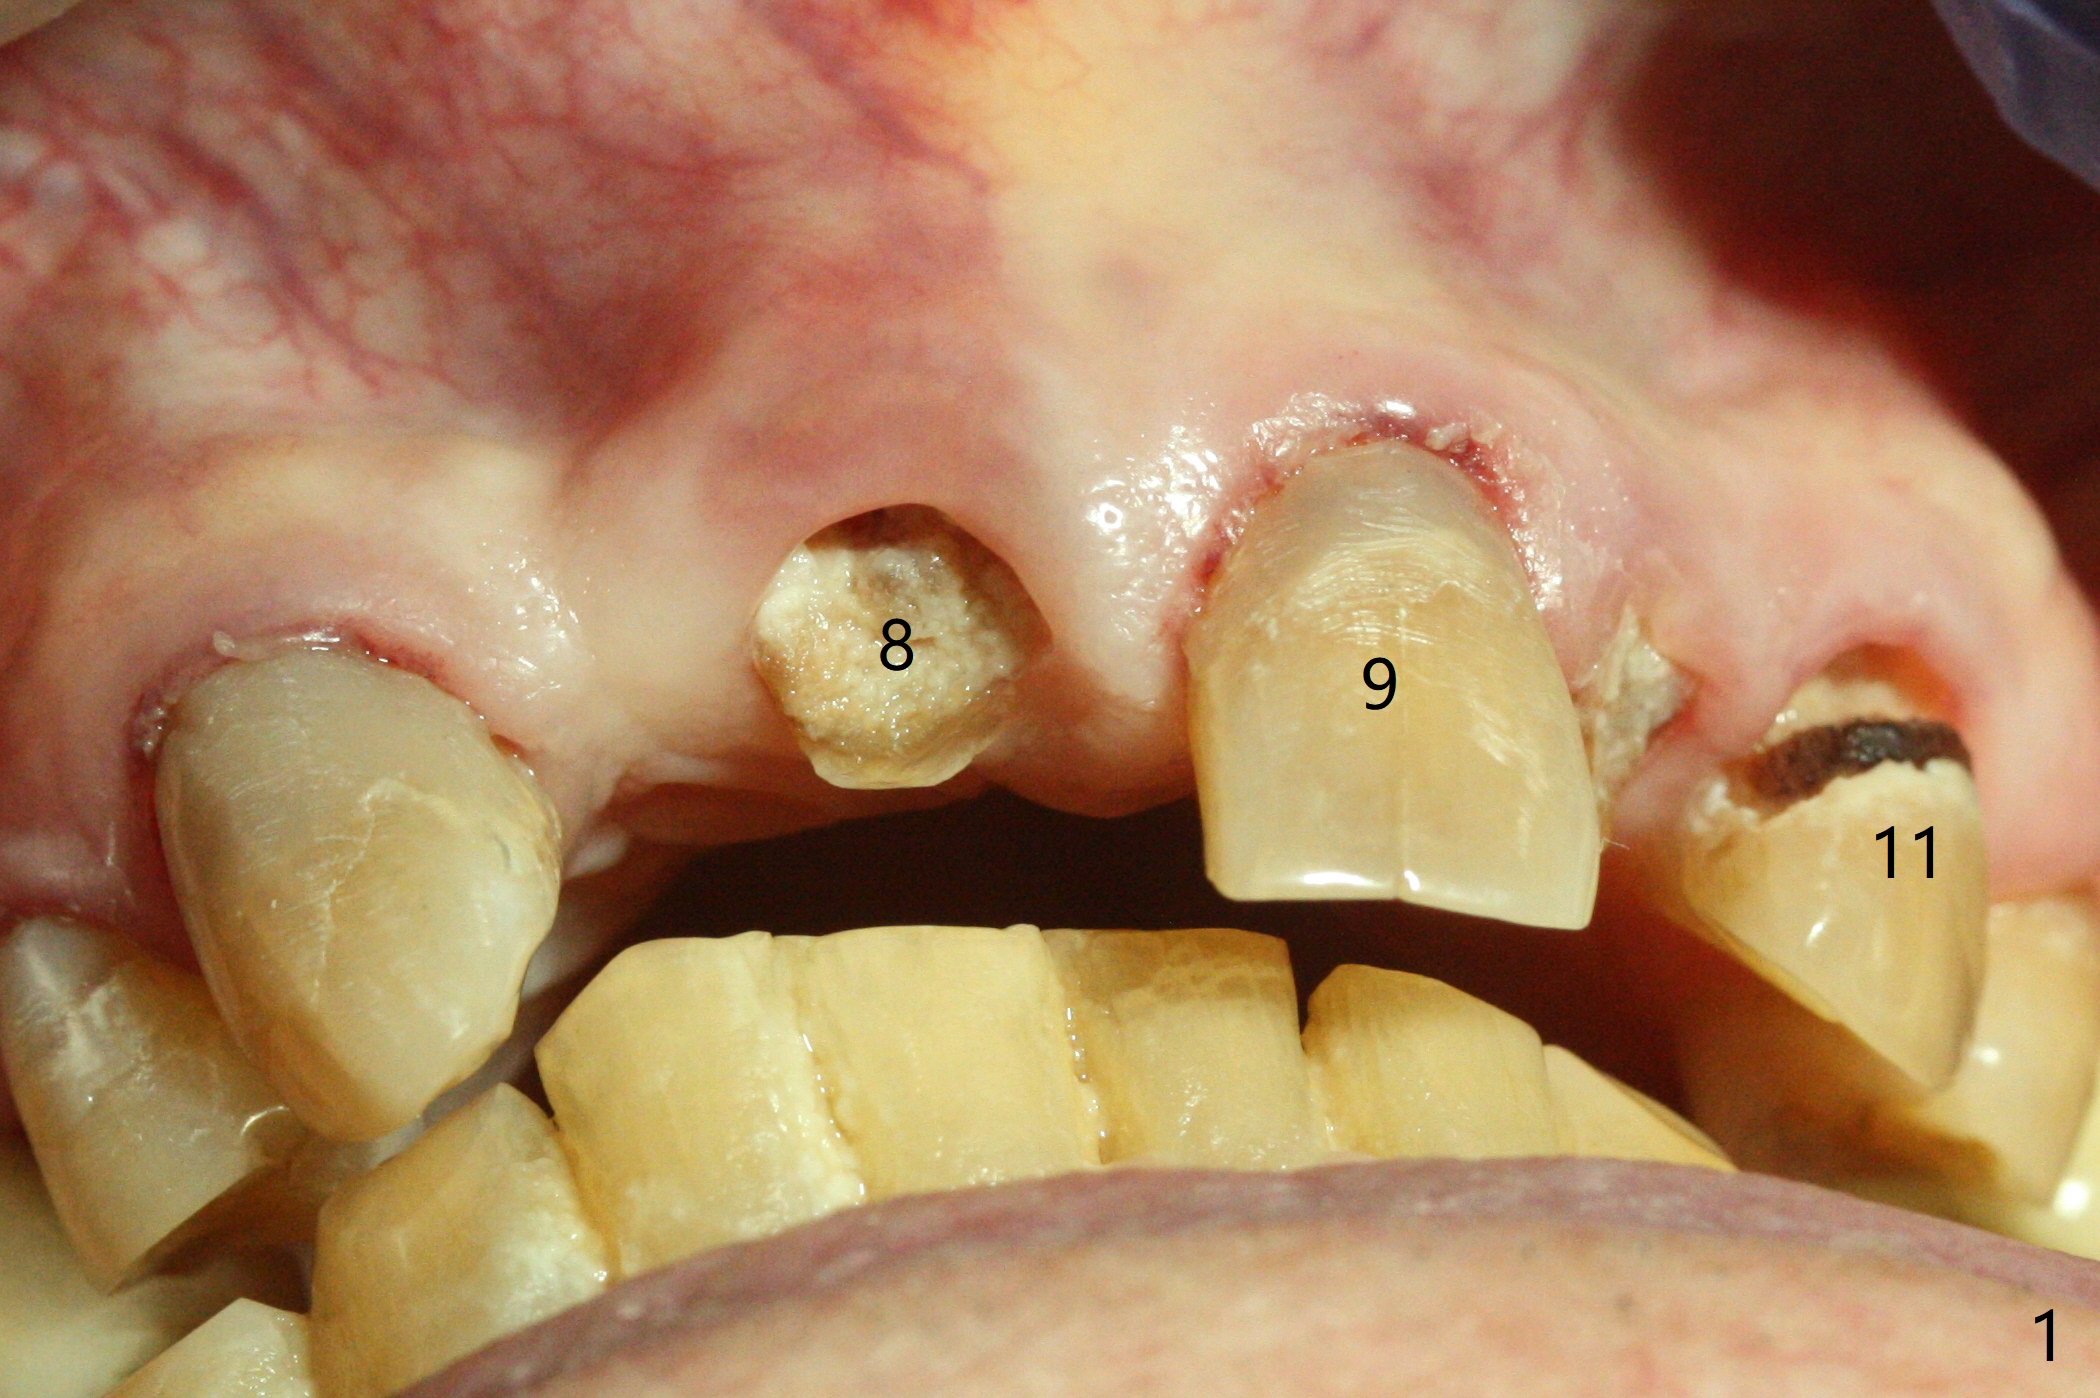

A 89-year-old man has poor dentition (Fig.1). After caries control (Fig.2), implants are placed at #7 and 8 (Fig.3). Because of the buccal plate fracture associated with extracted the ankylosed tooth #8, postop gingival recession occurs (Fig.3 arrow). To prevent the complication, socket shield will be performed if extraction of the tooth #10 turns out to be difficult. A 2.5 or 3x16 mm 1-piece or 3.5x13 mm/3.8x15 mm 2-piece implant will be attempted to be placed. Take preop photos to show #7 and 8 crowns and #10 residual root . Incision may be made to expose the labial crest to make sure that the the remaining labial portion of the root is caries free after extraction with sectioning.